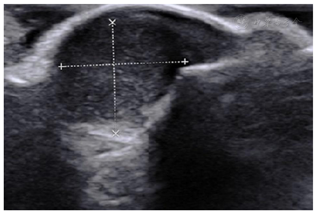

左足X线检查:未见明显异常;腰椎CT:腰椎退行性改变,L4椎体前滑脱,L4/5椎间盘膨出并后突;左足肌骨超声:左足第3趾甲深方低回声包块,考虑血管球瘤可能大(图1)。

结合症状体征及相关检查,考虑血管球瘤。术后病理证实为血管球瘤,大小1.2 cm×0.6 cm×0.3 cm。